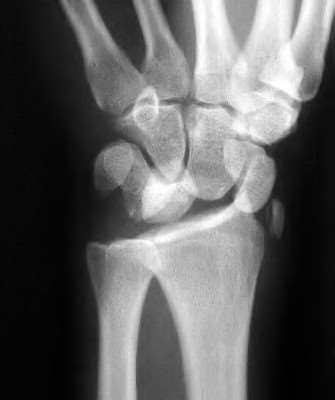

Question 6:

A 22-year-old male falls onto an outstretched hand and sustains a displaced fracture through the proximal pole of the scaphoid. Avascular necrosis of the proximal pole is highly likely due to the disruption of its primary vascular supply. Which vessel provides this critical retrograde perfusion?

Correct Answer: Dorsal carpal branch of the radial artery

Explanation:

The primary blood supply to the scaphoid is from the dorsal carpal branch of the radial artery, which enters the dorsal ridge of the scaphoid at the waist and courses proximally. This retrograde blood flow makes proximal pole fractures highly susceptible to avascular necrosis and nonunion. The superficial palmar branch provides a minor supply (about 20%) to the distal pole.